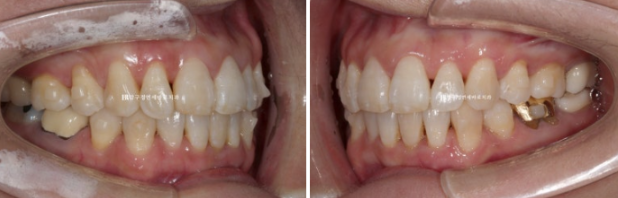

파란 화살표 부분은 잇몸이 주변치아에 비해 내려가있습니다

그 이유는 배열에서 가장 벗어난 치아여서 입니다.

제자리로 넣어주면 잇몸이 회복되기도 합니다.

위 앞니 두개가 튀어나와있고 회전이 되어있습니다.

정식용어는 아니지만 이것을 나비치아 라고 부릅니다.

23.07~24.05

배열에서 가장 많이 벗어난 덕분에 잇몸이 유독 내려갔던 치아를 자세히 보겠습니다.

잇몸 퇴축이 회복이 되어 치아뿌리 노출이 줄었습니다.